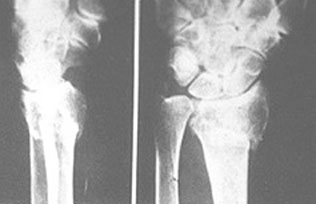

Colles'Fracture เป็นกระดูกหักที่ส่วนปลายของ radius พร้อมด้วย dorsal angulation ของชิ้นส่วนปลาย มากกว่าครึ่งหนึ่งจะมี avulsion fracture ของ ulnar styloid process ร่วมด้วยเป็นกระดูกหักของบริเวณข้อมือที่พบบ่อยที่สุด โดยเฉพาะในผู้สูงอายุ ดังรูป sk 85

รูป sk 85 Colles' fracture แสดง dorsal fragment ของ radius